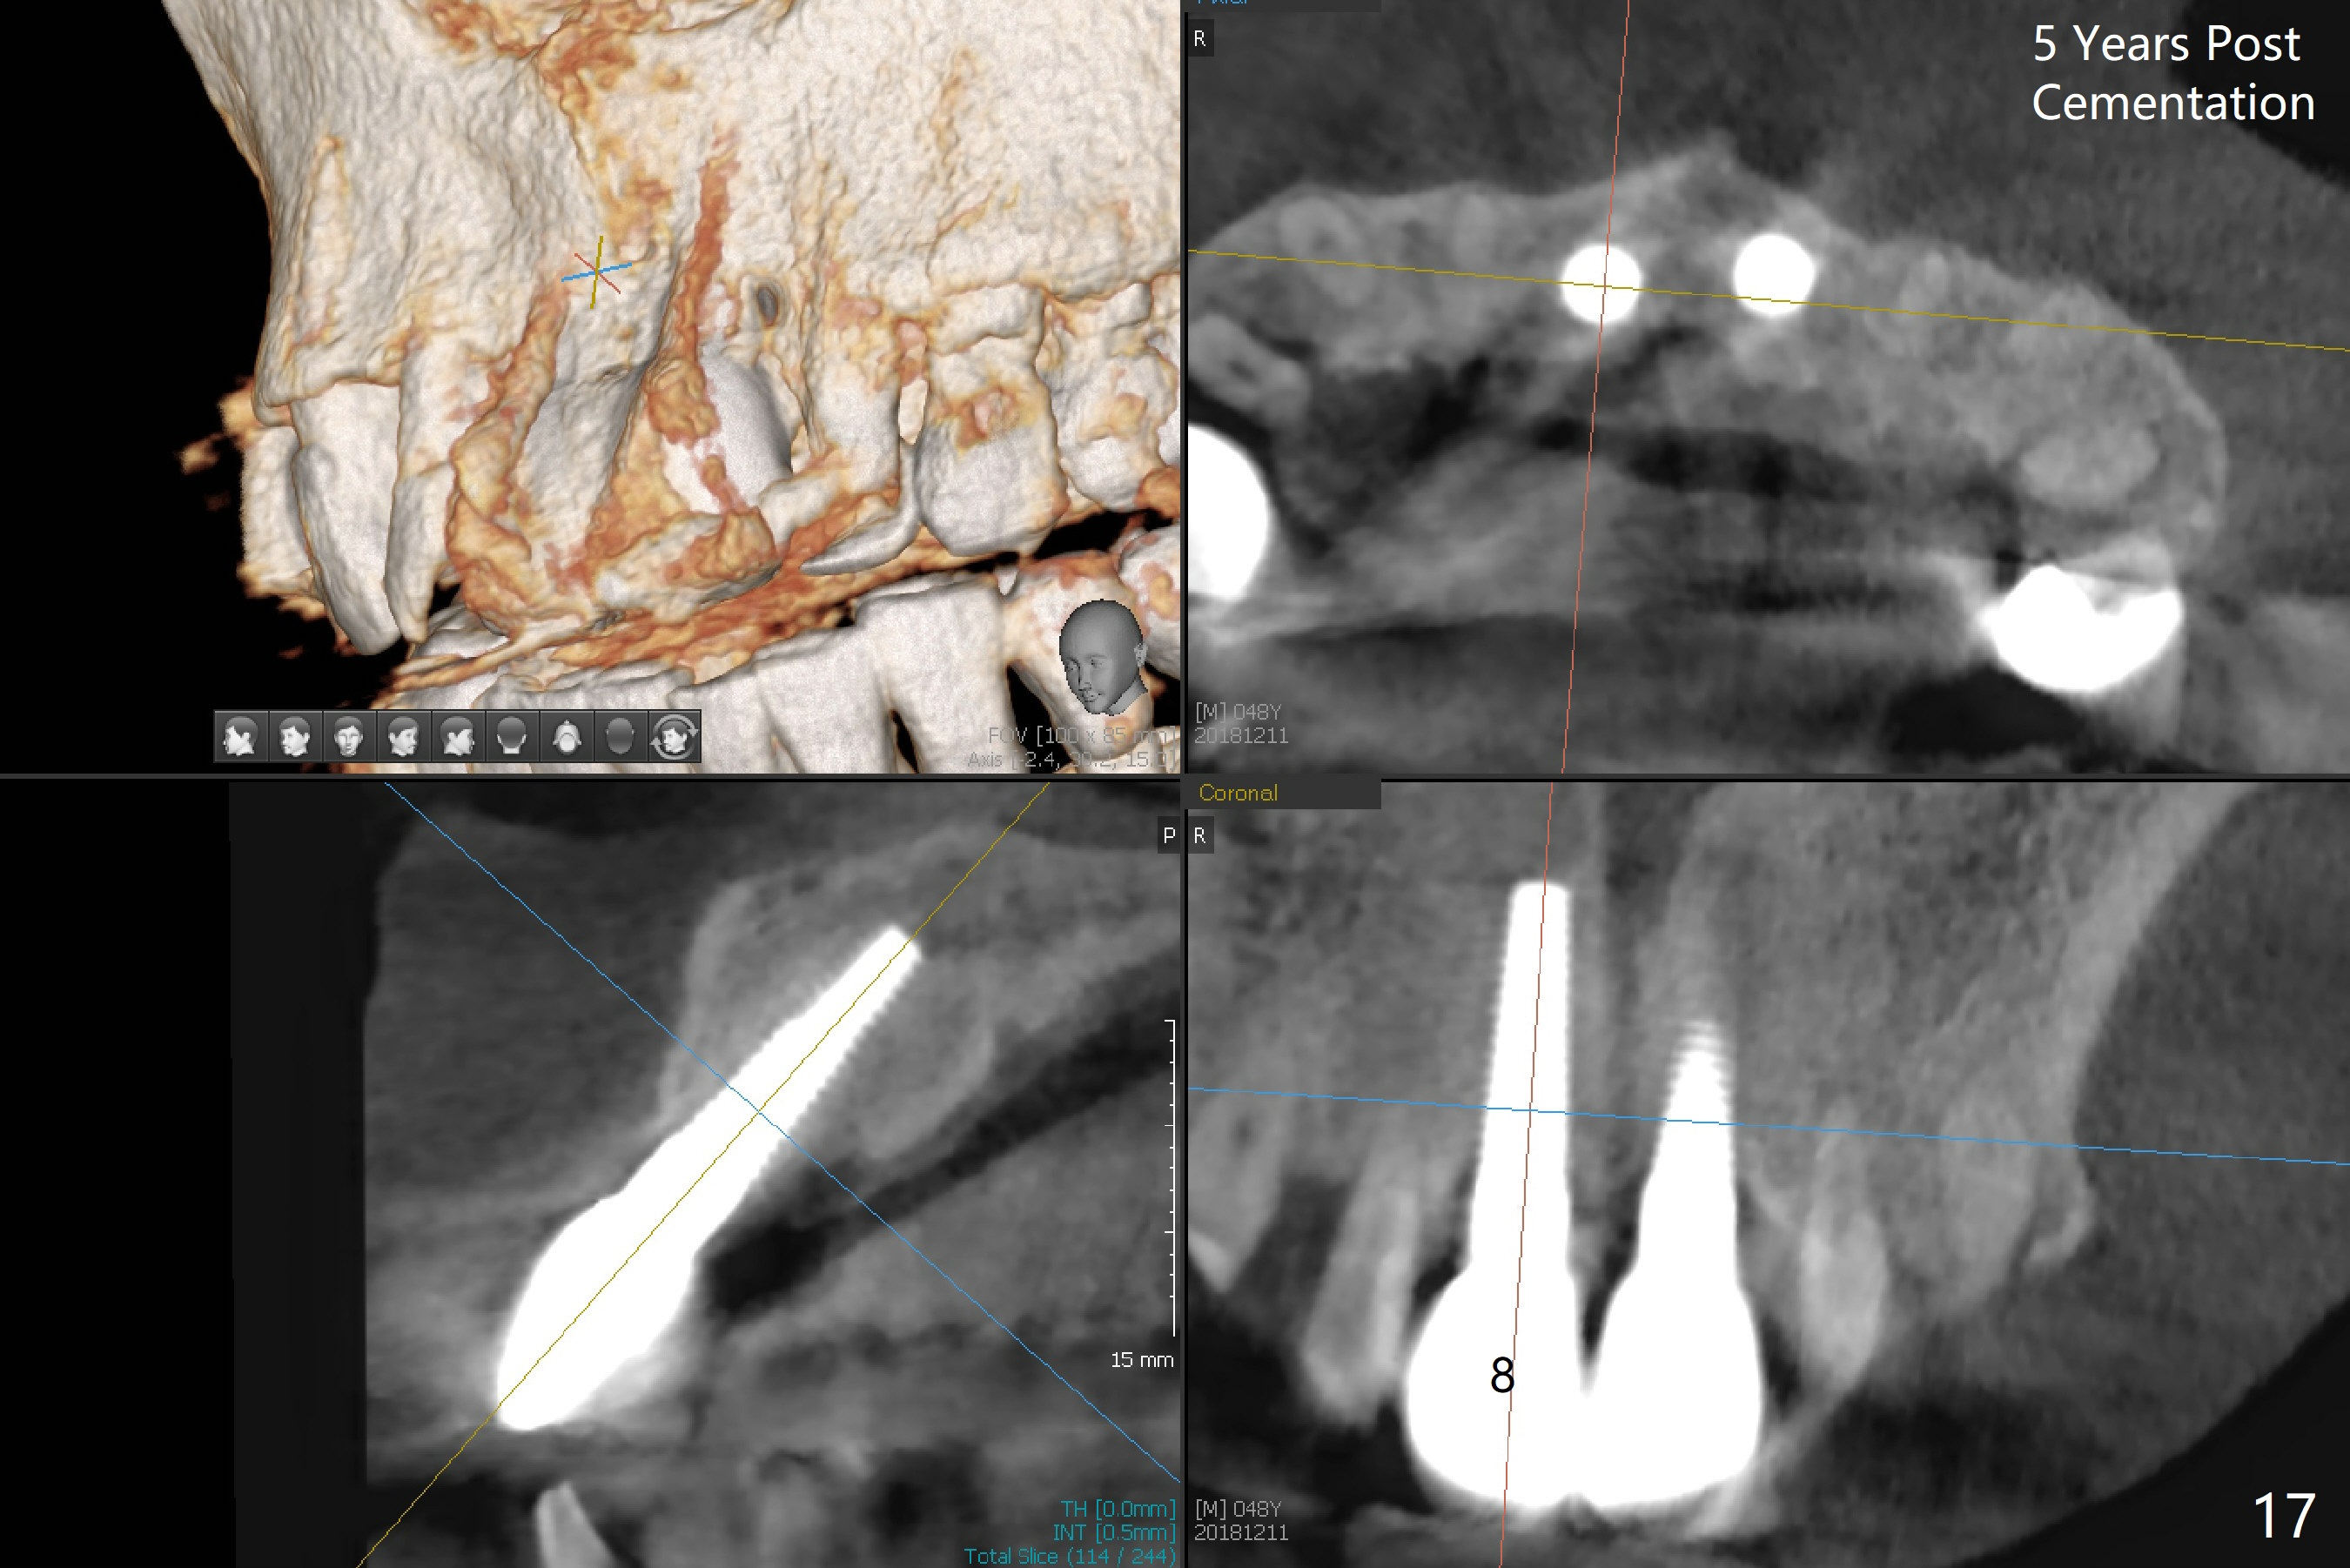

Definitive restoratons (Zirconium crowns) are seated (Fig.15,16). There is no sign of infection. The patient is pleased. In fact the nasal floor does not seem to have been lifted by the implants, as revealed by CT taken 5 years post cementation (Fig.17,18).